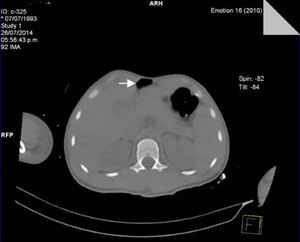

Seventy-two hours after admission, the patient presented subcutaneous emphysema in the anterior chest extending to the neck, a simple CT scan was performed of the chest and abdomen which revealed a pneumomediastinum, bilateral lung contusions and pneumoperitoneum (Figs. 2 and 3). He continued on mechanical ventilation. Oesophageal injury was ruled out by oesophagogram with water-soluble contrast medium, and flexible bronchoscopy ruled out tracheobronchial injury. Furthermore, no signs of peritoneal irritation were found, therefore the Macklin effect was established as the cause of the pneumomediastinum and pneumoperitoneum.

In cases where the chest X-ray is normal (fewer than 10%), the study of choice is CT, which is considered the gold standard, even in patients with suggestive radiological findings.1,10 The Macklin effect appears as a linear collection of air contiguous with the bronchovascular sheath and the characteristic findings of interstitial emphysema due to the Macklin effect present as a triad: (1) interstitial emphysema, (2) to the bronchus, and (3) to the pulmonary blood vessel.3,16 CT has high sensitivity to pneumomediastinum and pneumoperitinoneum (>95%) and specificity (>85%) in order to rule out major injury to the aerodigestive tract. However, the possibility of an oesophageal or tracheal injury should always be ruled out using other diagnostic methods.10

The presence of a pneumoperitoneum is generally associated with perforation of the hollow viscera and therefore requires emergency surgery; in 5–15% of cases it is not the result of visceral perforation and most of the time is associated with medical interventions.17 Mularski et al.17 identified 2 groups as non-surgical causes of pneumoperitoneum: (1) abdominal cause (post-operative air, peritoneal dialysis, endoscopic gastrointestinal procedures), and (2) thoracic cause (mechanical ventilation, cardiopulmonary resuscitation, lung trauma injuries, pneumothorax) which indicate that when abdominal pain and distension are minimal, and when peritoneal signs, fever and leukocytosis are absent, nonsurgical causes should be considered.17,18